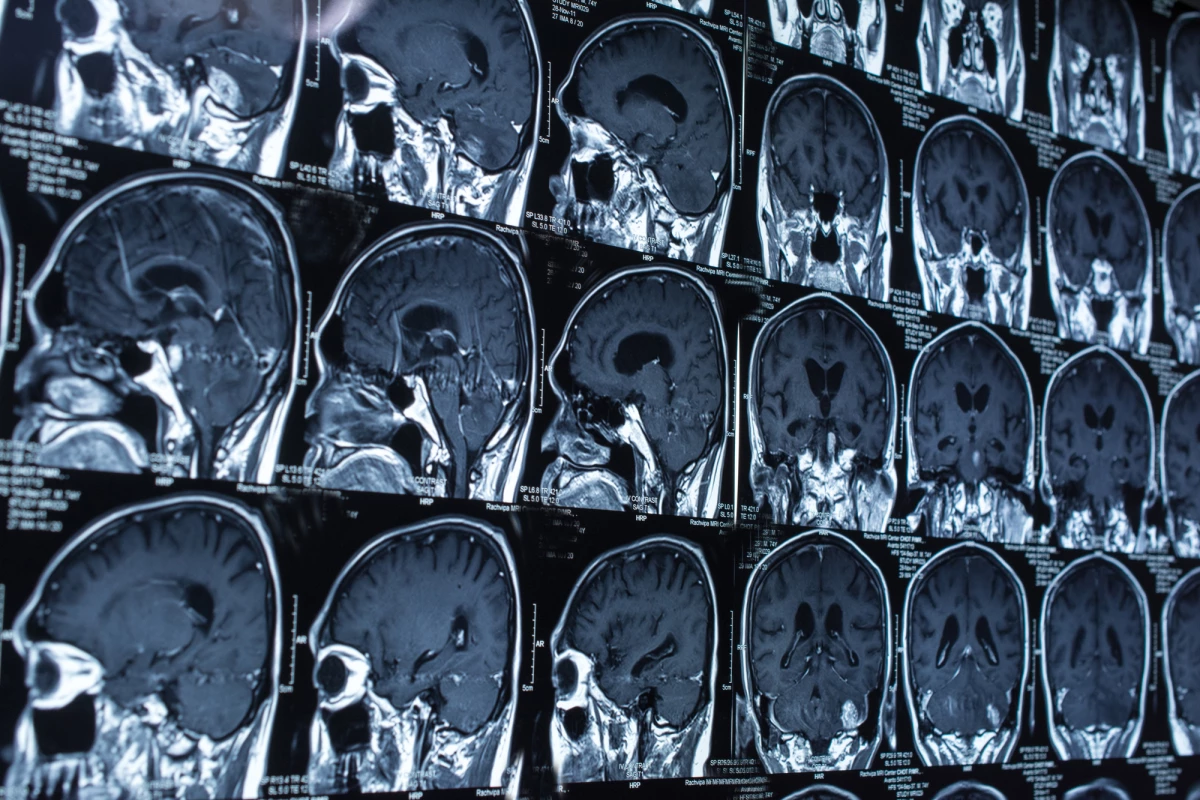

Brain injuries can vary greatly in their severity, but assessing the extent of the damage is far from a simple undertaking. Scientists in the UK have developed a new AI algorithm that could help narrow the margin for error, with the ability to detect and categorize different types of brain lesions to gauge the impact of an injury.

One of the tools doctors use to assess brain injuries is a CT scan, which can reveal signs of damage, such as lesions, on the brain. But analyzing these scans to reach a diagnosis is a time-consuming process for radiologists, and given the complex nature of the organ, it can see tell-tale signs often overlooked.

Menon and his research team, which includes scientists from Imperial College London, set out to develop an AI tool that could automate the classification of brain lesions in patients with head injuries. The researchers began by training the AI on more than 600 CT scans featuring brain lesions of different sizes and types.

The machine learning tool was then put to work on another set of CT scans, where it proved capable of classifying the volume of the brain lesions and their progression. Like the teams behind a number AI-powered medical diagnostic tools, the researchers see real potential in their technology to spot things that humans cannot.